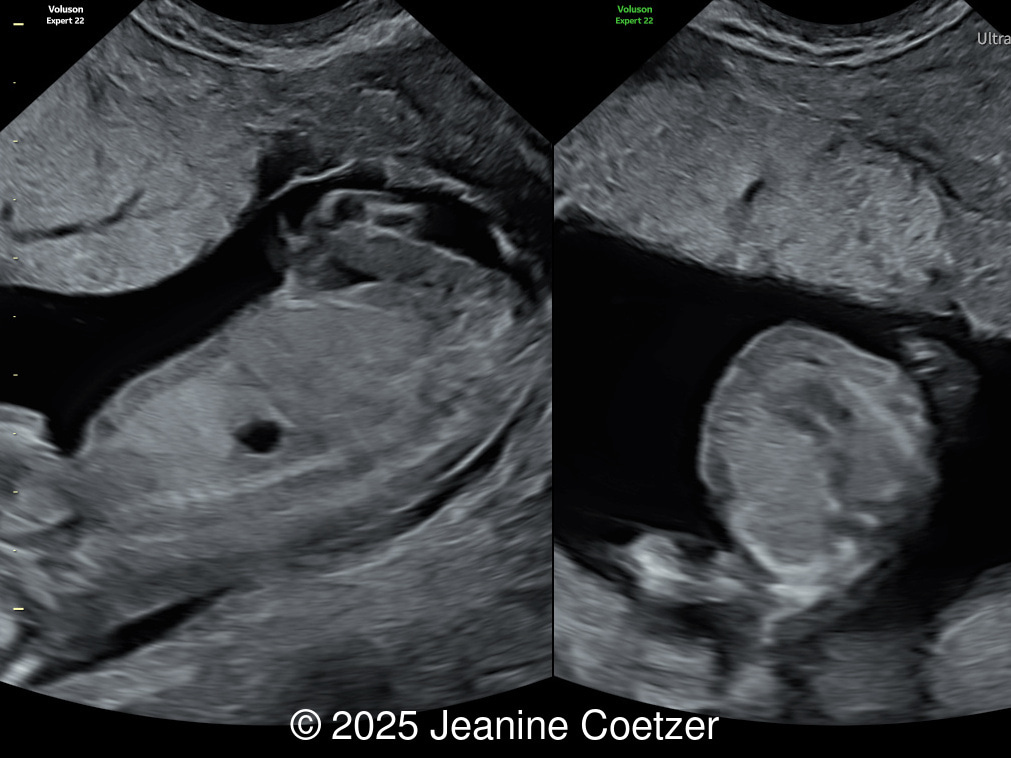

38-year-old woman with no significant previous medical history presented for her first scan at 13 weeks. This was her first pregnancy and was conceived through in vitro fertilization abroad.

We present a case of Congenital Diaphragmatic Hernia diagnosed in the first trimester.

Our imaging revealed a left-sided congenital diaphragmatic hernia with the stomach located in the left hemithorax causing significant mediastinal shift, and right cardiac axis deviation. The four cardiac chambers and outflow tracts appeared normal. Invasive genetic testing was declined. The parents were committed to the pregnancy and did not return for follow up.